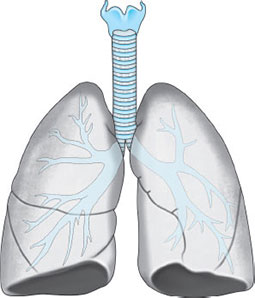

The Lungs (Fig. 13)

Each lung is roughly conical, with an apex, a base, a lateral (or costal) and a medial surface and with three borders—anterior, posterior and inferior. Each lung lies freely within its pleural cavity apart from its attachments at the hilum. The right lung is the larger, weighing on average 620 g compared with 570 g on the left. The lung of the male is larger and heavier than that of the female. Each lung is divided by a deep oblique fissure, and the right lung is further divided by a transverse fissure. Thus, the right lung is trilobed and the left bilobed.